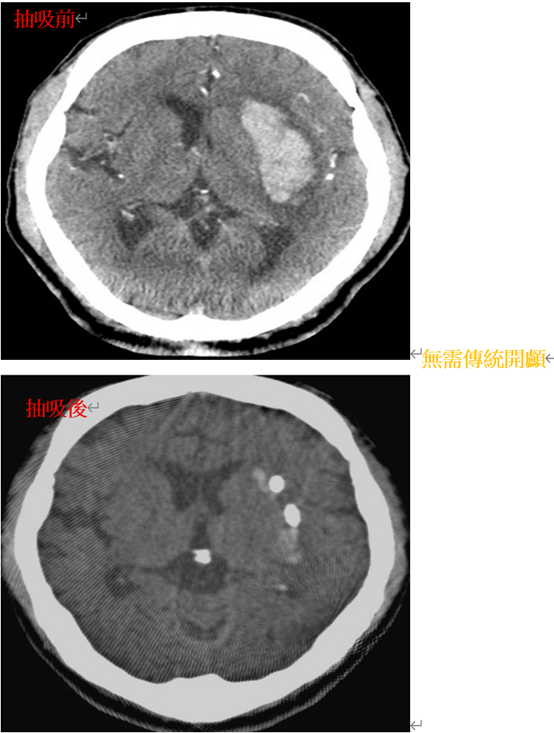

精準微創腦出血抽吸手術

這是一種微創腦出血手術,取代傳統開顱的方式,將腦部的血塊移除。這種手術方式僅需在頭顱鑽一個孔,並在電腦導航系統輔助下,精準到達血塊位置,降低對大腦組織的破壞,恢復時間較短,可加快患者術後肢體力量的恢復。未來並將導入即時術中電腦斷層系統,在術中即時獲得患者腦部最新資訊,不浪費一分一秒搶救腦部的黃金時間,讓每個來到本院的患者,都能得到最即時,最先進,最優質的醫療服務,以期得到最好的預後。